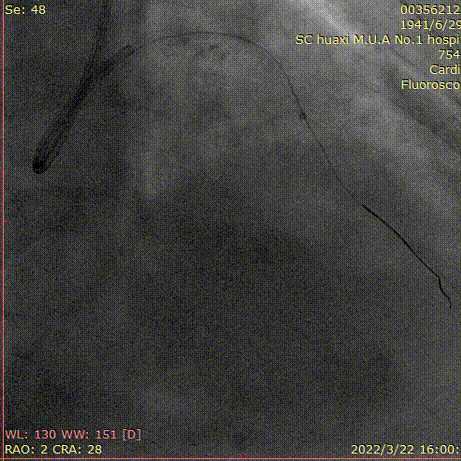

造影说明:前降支开口重度狭窄,近段闭塞,入口不清,闭塞段长,走形不清。自身可见桥侧支形成,远端血管细小。

说明:XB3.0指引导管,Finecross微导管,XTR,XTA导丝反复调整,导丝进入闭塞段,前进阻力大,考虑在内膜下。

说明:先后使用XTA,Pilot200,导丝仍在内膜下。